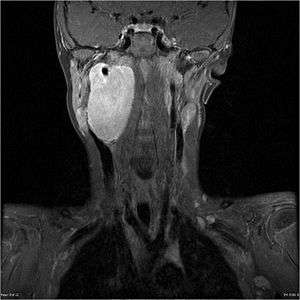

MRI of a ganglioneuroblastoma found in the head and neck of a 7 year old Caucasian male.

Ganglioneuroblastoma is a variant of neuroblastoma that is surrounded by ganglion cells.